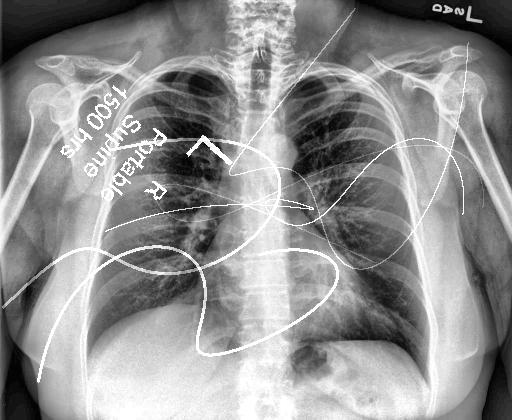

Automated catheter detection is a challenging task. Although most catheters have a radiopaque strip to facilitate detection, the strip may become less apparent depending on the projection angle. Catheters maybe confused by other similar linear structures like ECG leads and anatomy including ribs. Additionally, portions of catheters can be occluded by anatomical structures given that radiographs are a 2D projection of a 3D structure. For example, when a NGT is placed within the oesophagus, the catheter itself becomes less apparent due to the high density of the adjacent vertebrae. Finally, the number and type of catheters that could possibly appear in pediatric X-rays are unknown a priori. The catheters may be intertwined with each other thus making simple line tracing methods fail. Figure 1 gives three sample pediatric X-ray images with some common catheters highlighted in different colors.

To alleviate this annotation problem in catheter detection, we proposed to use X-ray images with simulated catheters by exploiting the fact that catheters are essentially tubular objects with various cross sectional profiles. To be more specific, a synthetic 2D projection of a catheter is generated by first simulating a horizontal catheter profile and then using it as a brush tip to draw along a B-spline path. This generated catheter is then composited with an X-ray image serving as the training data. Another contribution of this work is a segmentation network that can inherently take into account multi-scale information. This network adopts a UNet-style form and contains a recurrent module that can process inputs with increasing scales111Our code is available at https://github.com/xinario/catheter_detection.git.. We have empirically shown that by iterating through the scale space of the input image, higher recall is achieved as compared to using a single scale. Details about the methods are discussed in Section 3. Three sample detection results are shown in Figure 1.

The test dataset is collected locally and only contains frontal chest-abdominal X-rays from patients < 4 weeks old. This is the most common radiograph obtained to confirm placement of catheters such as UACs and UVCs in neonates. Currently, the test set has 35 fully labeled images with different catheter types with sample images previously shown in Figure 1. All the annotated catheters (lines excluding ECG leads) are treated as the same class in the detection.